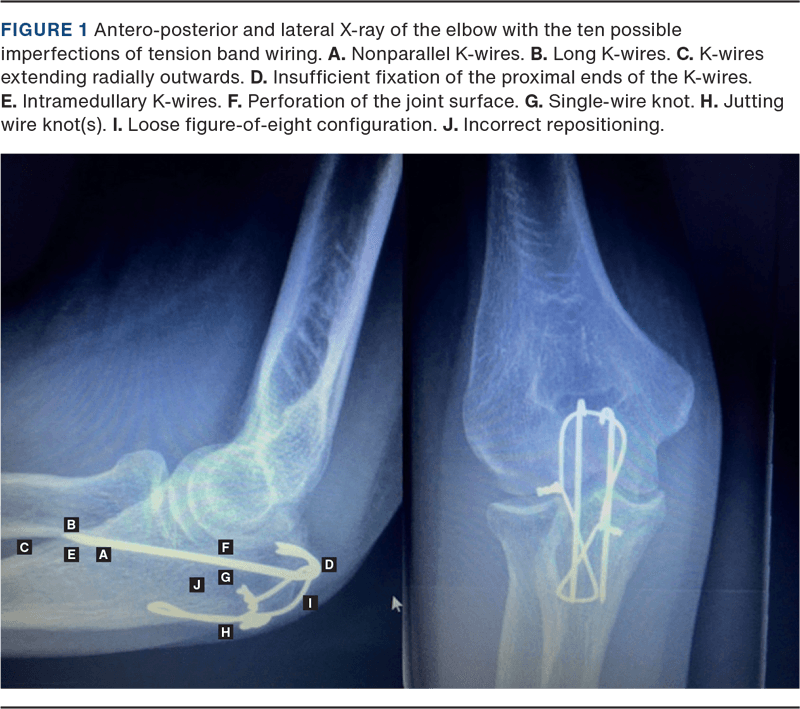

It is well known that there is an association between the quality of osteosynthesis and subsequent complications [13-15]. For olecranon fractures, one study [9] described ten criteria for evaluating TBW treatment based on ten operative imperfections, including nonparallel or long K-wires, insufficient fixation of the proximal ends of the K-wires, perforation of the joint surface, loose figure-of-eight configuration and incorrect repositioning [9]. So far, no studies have investigated whether an association exists between implant positioning (IMPO) of TBW in olecranon fractures and complications.

Patients’ healthcare files were reviewed for demographics, operation details, post-operative treatment and complications. Pre-operative X-rays were reviewed for classification using the Mayo classification [12], and perioperative or early post-operative X-rays were assessed for IMPO of TBW based on the ten imperfections presented by Schneider et al. [9] (Figure 1):

The number of imperfections was converted into an IMPO score of ten points, subtracting the number of imperfections; for example, if three imperfections were recorded, a seven-point IMPO score was assigned. Major complications were defined as any reoperation within eight weeks, reoperation due to deep infection, non-union or reosteosynthesis. Surgical complications were defined as major complications and the loss of TBW fixation. Minor complications included simple removal of hardware, defined as removal eight weeks after surgery due to discomfort in the elbow because of the osteosynthetic material.